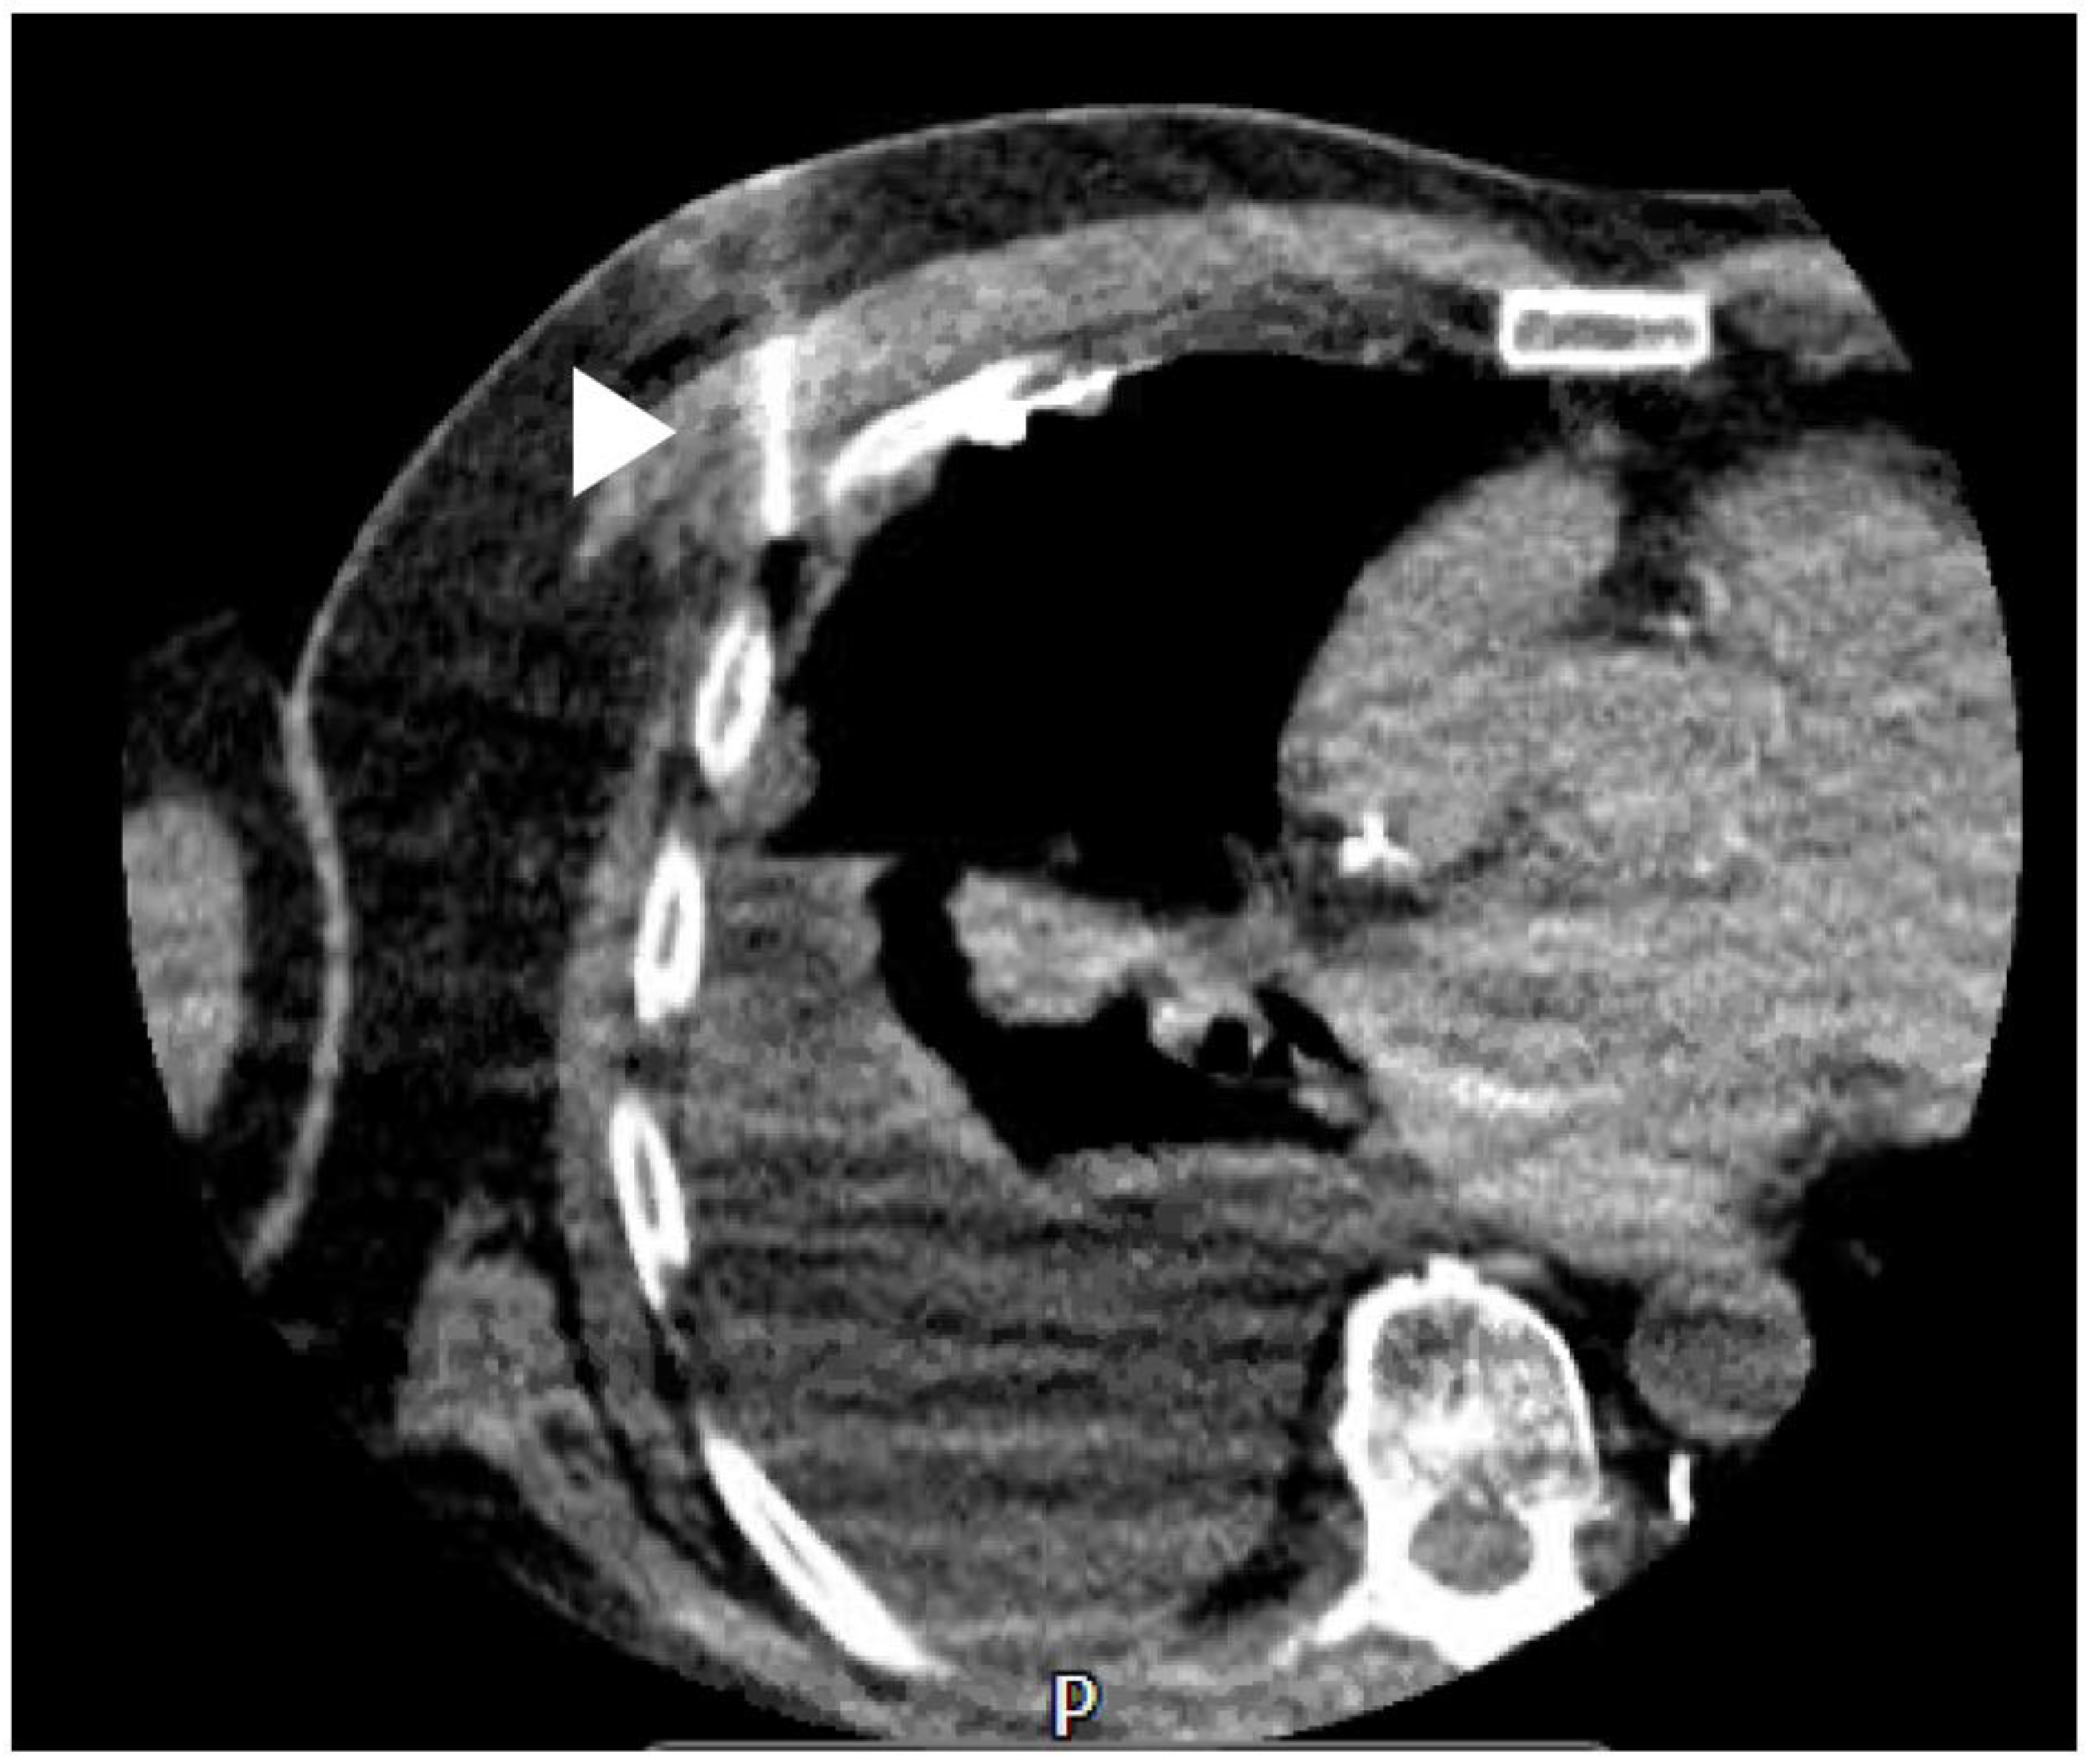

14. CT

- Tsim, S.; Stobo, D.B.; Alexander, L.; Kelly, C.; Blyth, K.G. The diagnostic performance of routinely acquired and reported computed tomography imaging in patients presenting with suspected pleural malignancy. Lung Cancer 2017, 103, 38–43. [Google Scholar] [CrossRef]

- Tsujimoto, N.; Saraya, T.; Light, R.W.; Tsukahara, Y.; Koide, T.; Kurai, D.; Ishii, H.; Kimura, H.; Goto, H.; Takizawa, H. A Simple Method for Differentiating Complicated Parapneumonic Effusion/Empyema from Parapneumonic Effusion Using the Split Pleura Sign and the Amount of Pleural Effusion on Thoracic CT. PLoS ONE 2015, 10, e0130141. [Google Scholar] [CrossRef] [PubMed]

- Porcel, J.M.; Pardina, M.; Alemán, C.; Pallisa, E.; Light, R.W.; Bielsa, S. Computed tomography scoring system for discriminating between parapneumonic effusions eventually drained and those cured only with antibiotics: CT for parapneumonic effusions. Respirology 2017, 22, 1199–1204. [Google Scholar] [CrossRef] [PubMed]

- Kim, J.S.; Shim, S.S.; Kim, Y.; Ryu, Y.J.; Lee, J.H. Chest CT findings of pleural tuberculosis: Differential diagnosis of pleural tuberculosis and malignant pleural dissemination. Acta Radiol. 2014, 55, 1063–1068. [Google Scholar] [CrossRef]

- Metintas, M.; Ucgun, I.; Elbek, O.; Erginel, S.; Metintas, S.; Kolsuz, M.; Harmanci, E.; Alataş, F.; Hillerdal, G.; Özkan, R.; et al. Computed tomography features in malignant pleural mesothelioma and other commonly seen pleural diseases. Eur. J. Radiol. 2002, 41, 1–9. [Google Scholar] [CrossRef]

- Traill, Z.C.; Davies, R.J.; Gleeson, F.V. Thoracic Computed Tomography in Patients with Suspected Malignant Pleural Effusions. Clin. Radiol. 2001, 56, 193–196. [Google Scholar] [CrossRef]